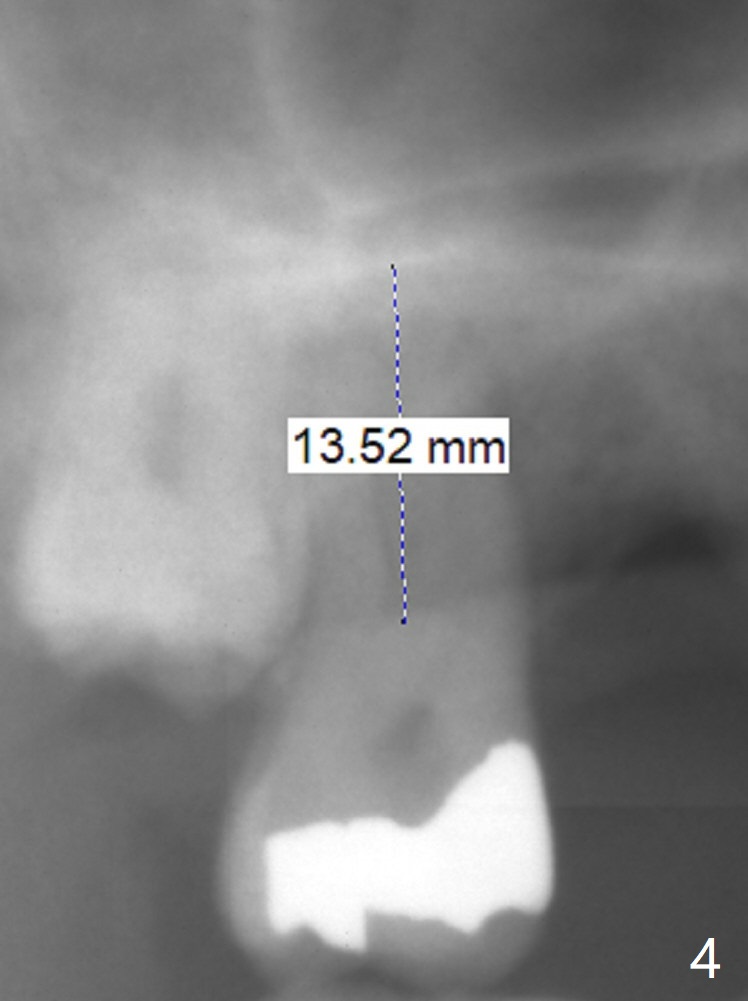

A 58-year-old man had 2 missing molar 3 years ago (Fig.1). Later the tooth #2 fractures with apparently severe bone loss (Fig.2). If the septum is lost, bone height is around 3 mm (Fig.3). Take PA before using Magic Sinus Lifter. Since his bone density is high, increase exposure time. If the septum is present (Fig.4), use Magic Drills sequentially (1.6, 2.8, 3.2 mm ....). PRF plug and membrane (1 each) are to be prepared.